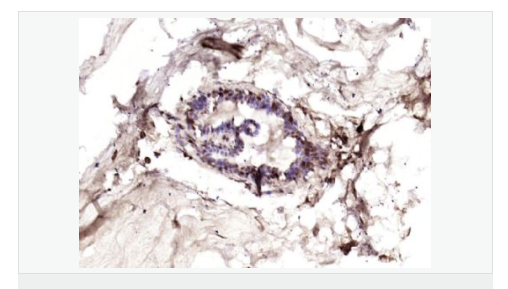

交叉反應(yīng):Human(predicted:Mouse,Rat) 推薦應(yīng)用:IHC-P,IHC-F,IF,ELISA

產(chǎn)品應(yīng)用ELISA=1:5000-10000 IHC-P=1:100-500 IHC-F=1:100-500 IF=1:100-500 (石蠟切片需做抗原修復(fù))